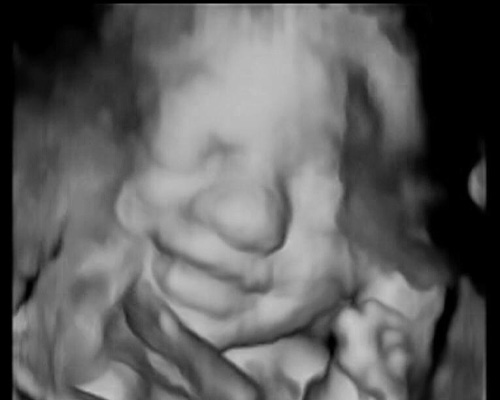

Ecografia del II trimestre (o morfologica)

L’ ecografia morfologica consente di confrontare le misure del feto con quelli delle curve di riferimento per valutare se le dimensioni corrispondono a quelle attese per l’epoca di gravidanza. Nello stesso esame si visualizzano la sede di inserzione placentare, la quantità di liquido amniotico e la struttura dei principali organi e distretti anatomici del feto.

Ecografia del III trimestre (o di accrescimento)

Nel terzo trimestre si effettuano misurazioni di alcune parti del feto, ed i valori di tali misure vengono confrontati con le curve di riferimento per valutare se corrispondono a quelle attese per l’epoca di gravidanza. In questo stesso periodo si visualizzano la sede di inserzione placentare la quantità di liquido amniotico ed alcuni organi fetali.